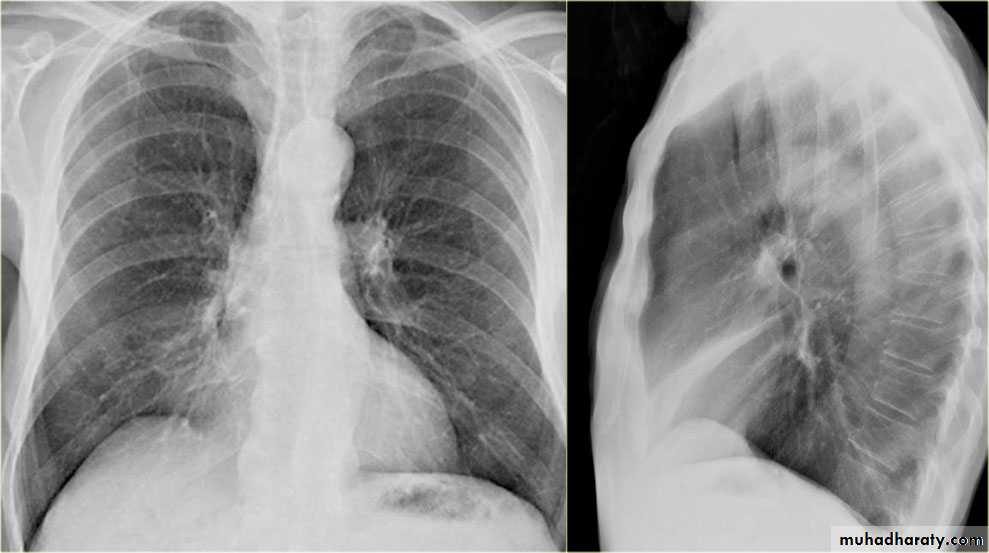

Fall from the 2nd floor